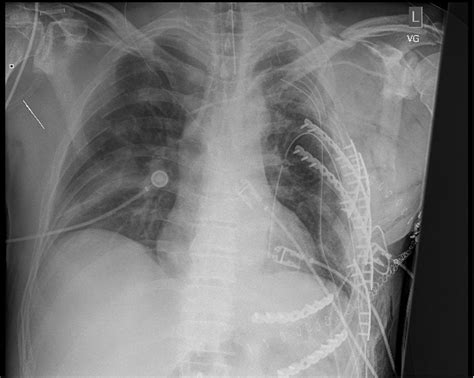

Orthopedic surgery tools and surgical environment